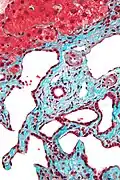

| Tinciones para fibras | ||||

| Tinción de Weigert | Tiñe fibras elásticas en tonos de azul y violeta. |

| ||

| Tinción con orceína | Tiñe fibras elásticas en tonos de marrón y negro. |